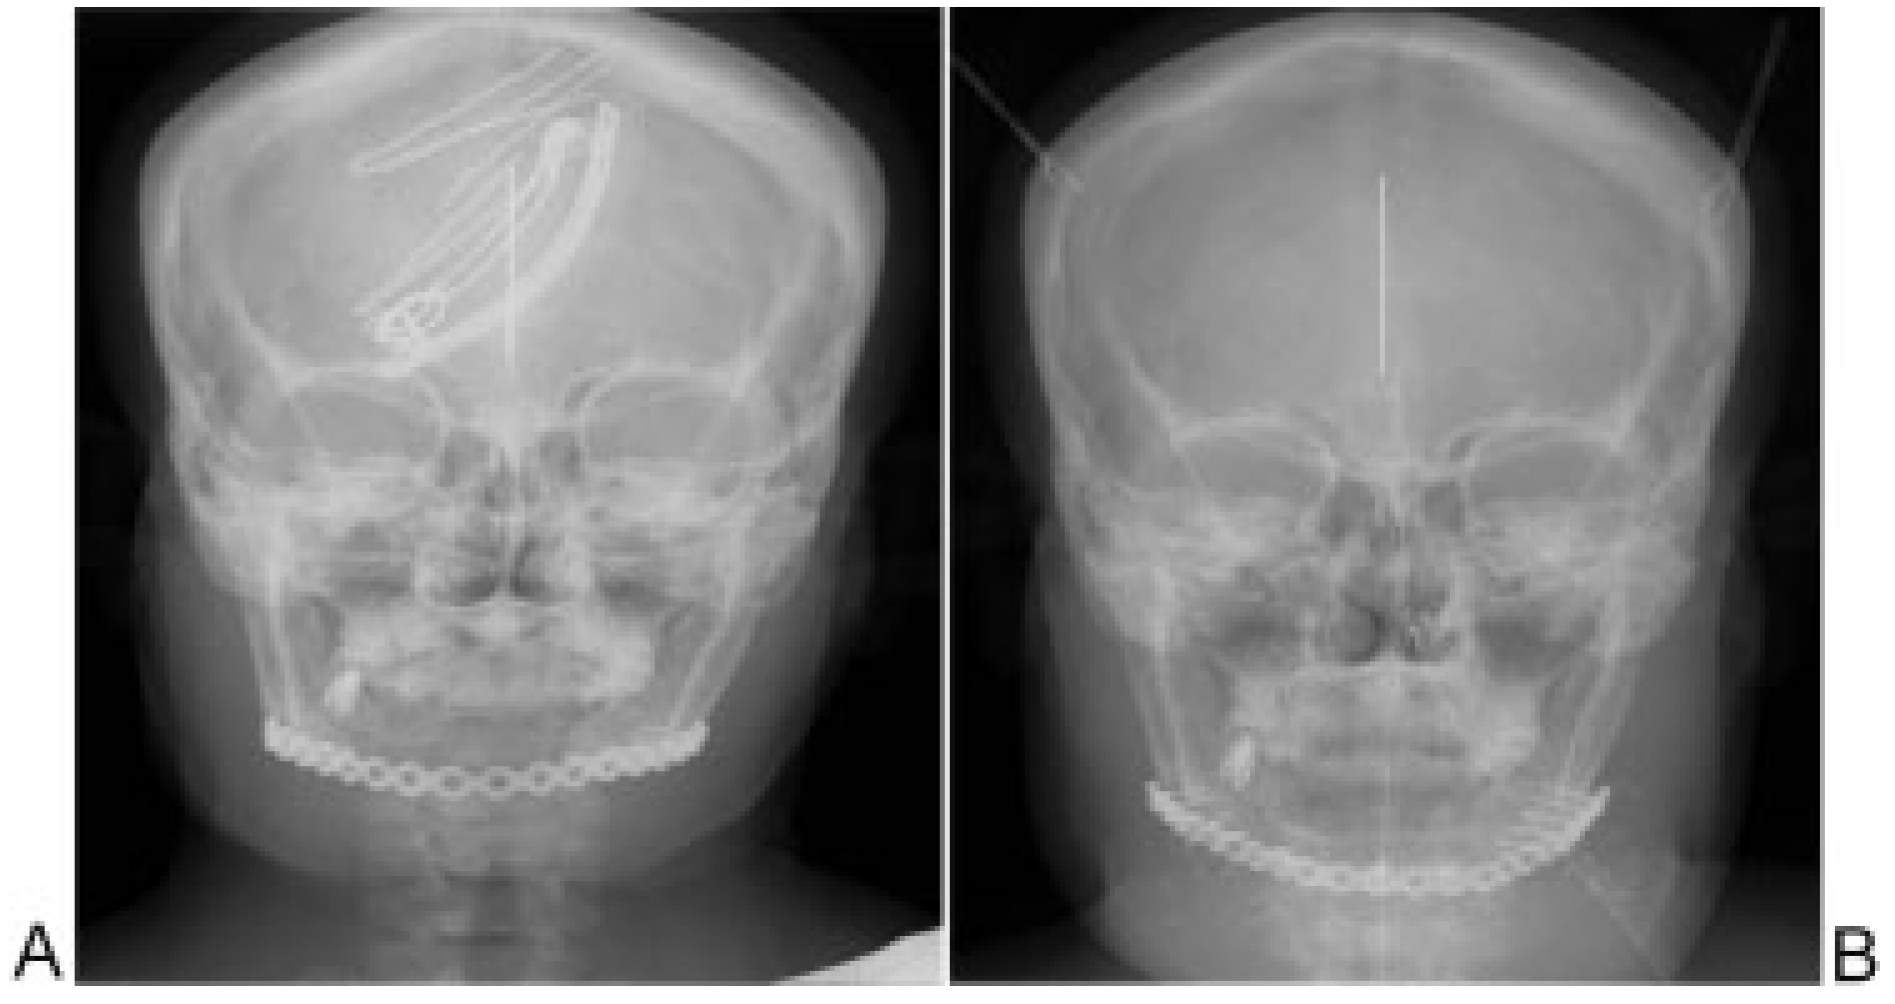

Postoperative radiographs confirmed the position of the intergonial angles remained unchanged (Figure 4A,B). Measurements were made of the intergonial and intercondylar widths on preoperative and postoperative anteroposterior cephalograms taken on the same machine. The preoperative intergonial and intercondylar widths were 83.5 and 111.4 mm, respectively. The postoperative intergonial and intercondylar widths were 82.1 and 112.1 mm, respectively.

Figure 4. (A) Preoperative anteroposterior cephalogram, demonstrating intergonial and intercondylar widths of 83.5 and 111.4 mm, respectively. (B) Postoperative anteroposterior cephalogram, demonstrating preserved intergonial and intercondylar widths, as well as mandibular symphysis reconstruction with free fibula. The postoperative intergonial and intercondylar widths were 82.1 and 112.1 mm, respectively.